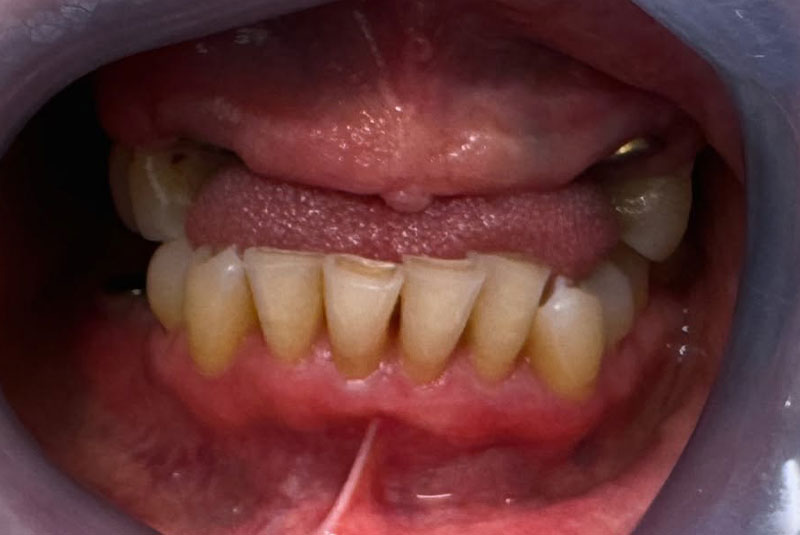

Before After